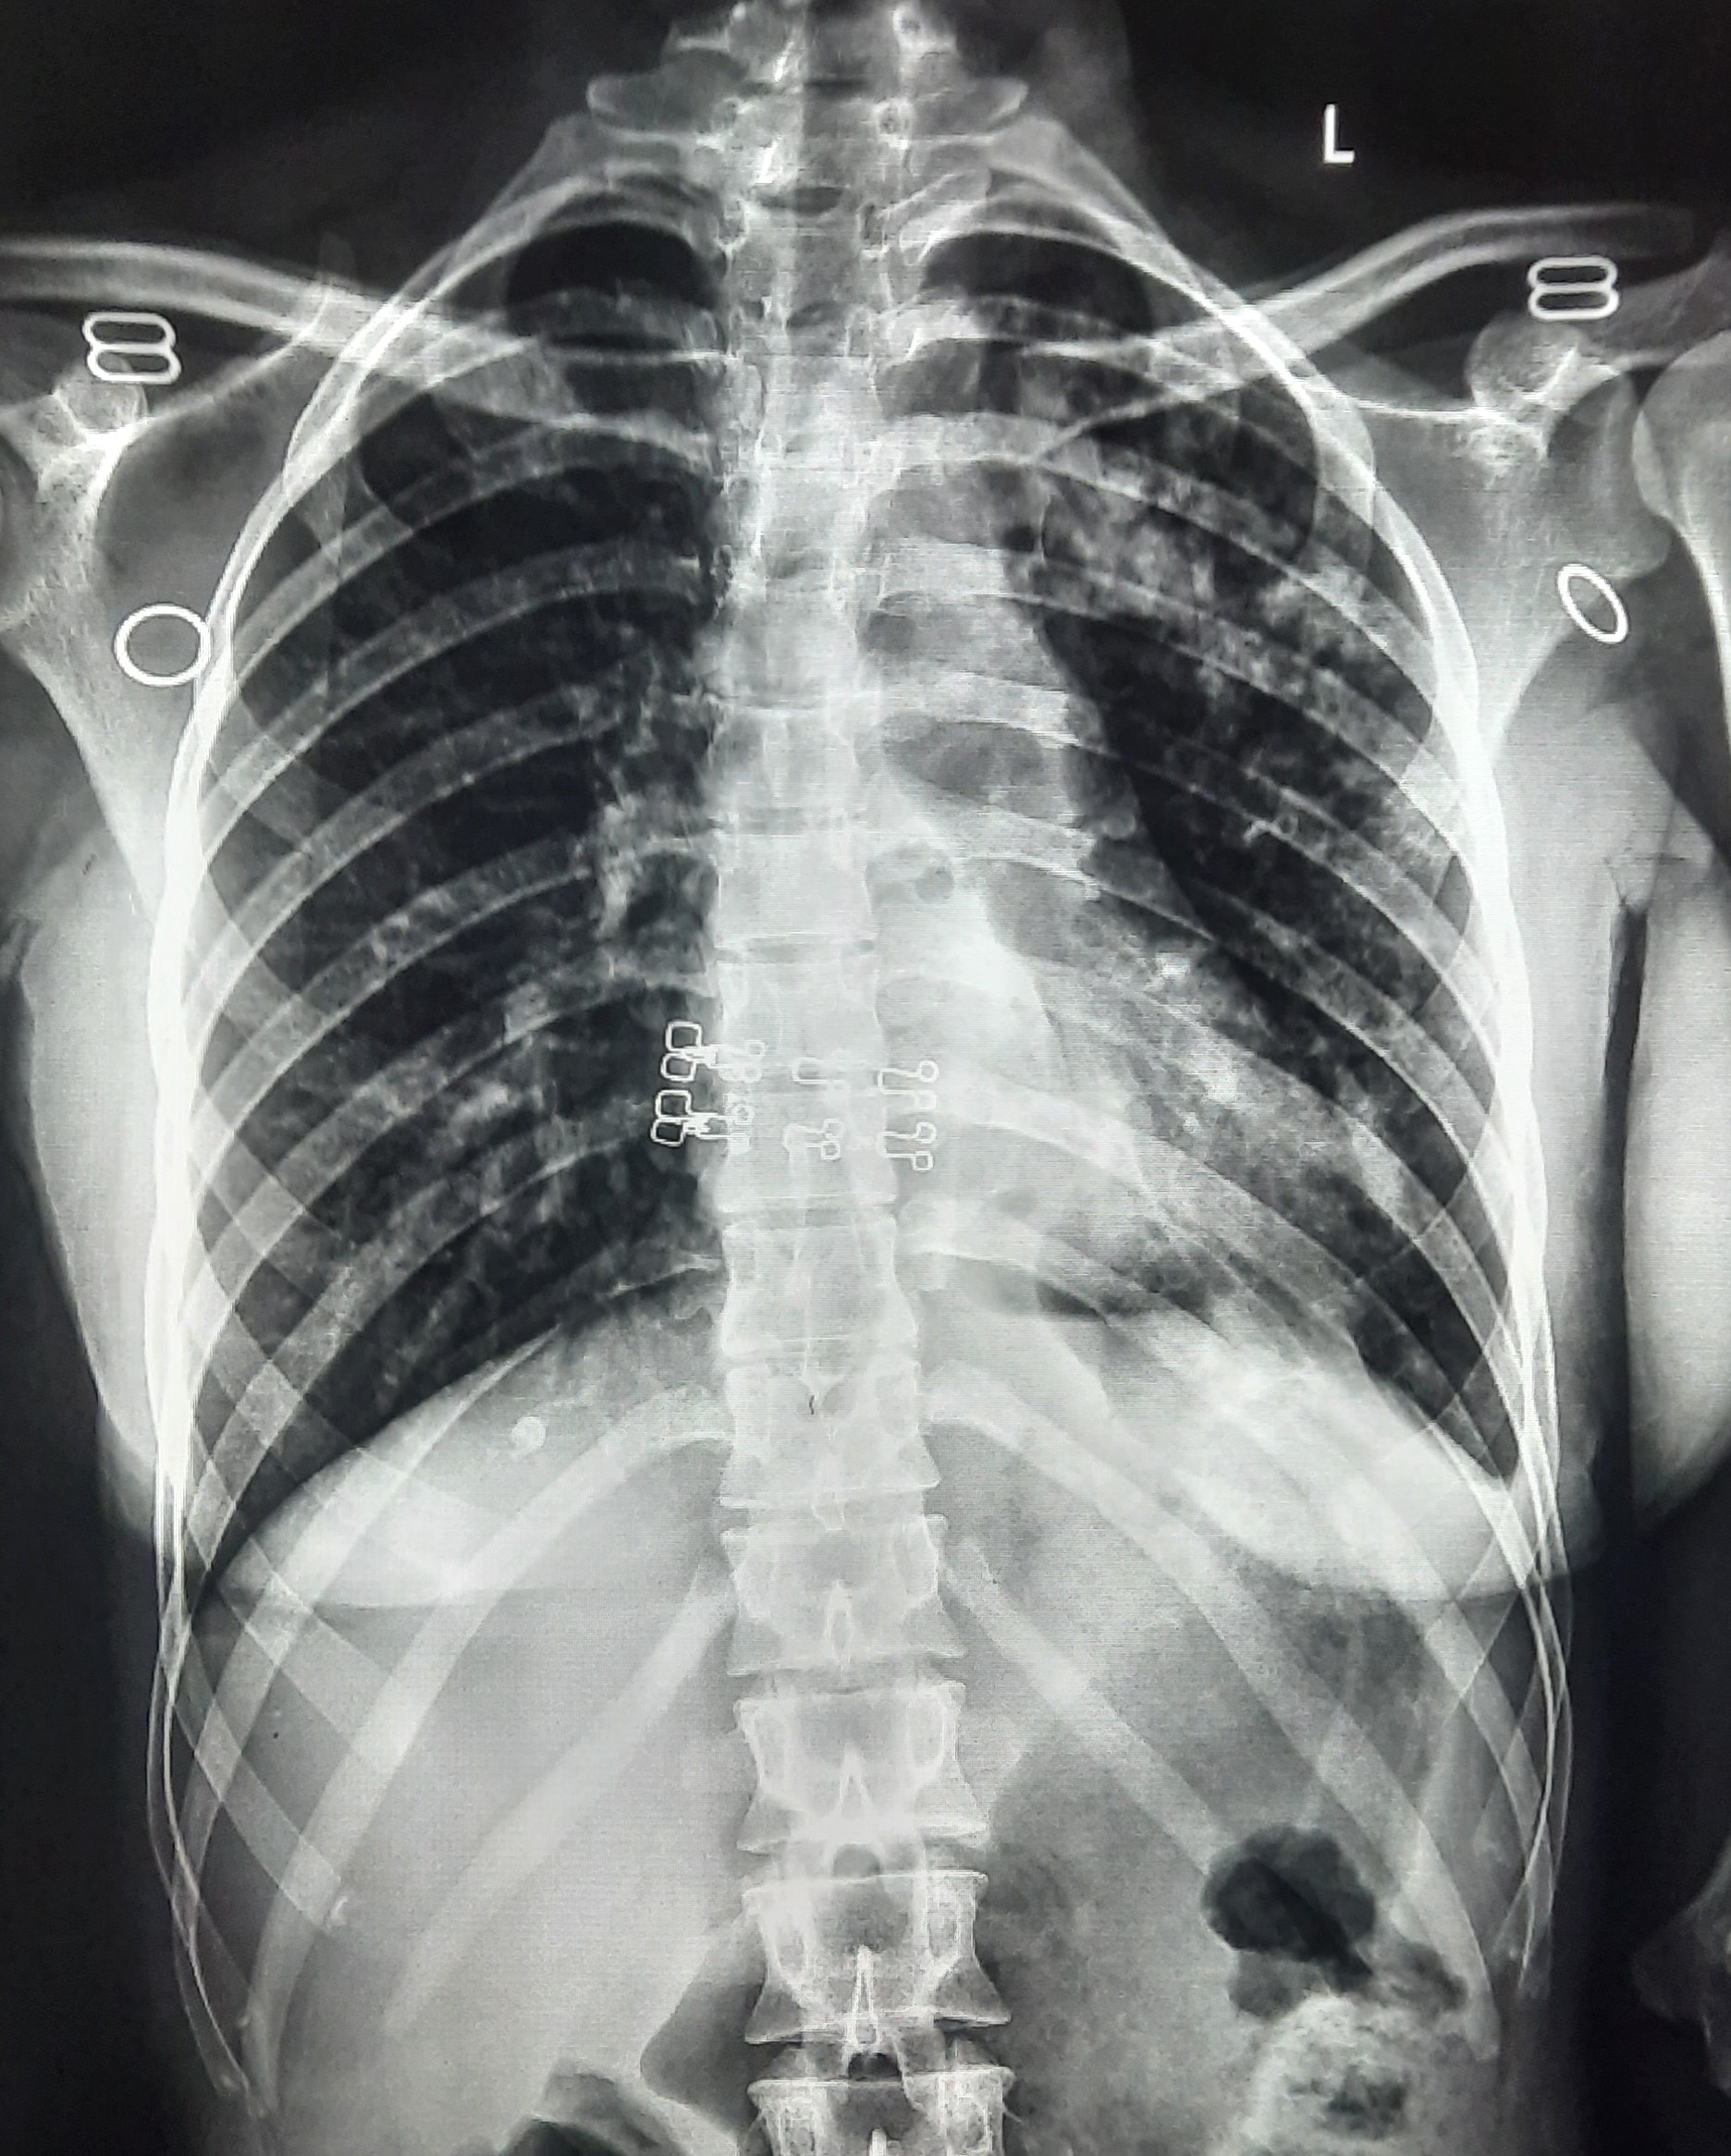

| 51 | IGGMC, Nagpur, Nagpur | P2 | 29-4421 | Santosh Neware | Consent taken on Paper | 40 Yrs. |

Provisional Diag : Pulmonary Tuberculosis

Final Diag : Pulmonary tuberculosis (Microbiologically Confirmed PTB) |

TB Case (Confirmed) | Right Upper & mid zone fibro cavitary lesion present, upward pull of right hemidiaphragm, tracheal pull right sided | Abnormality visible on x-ray |